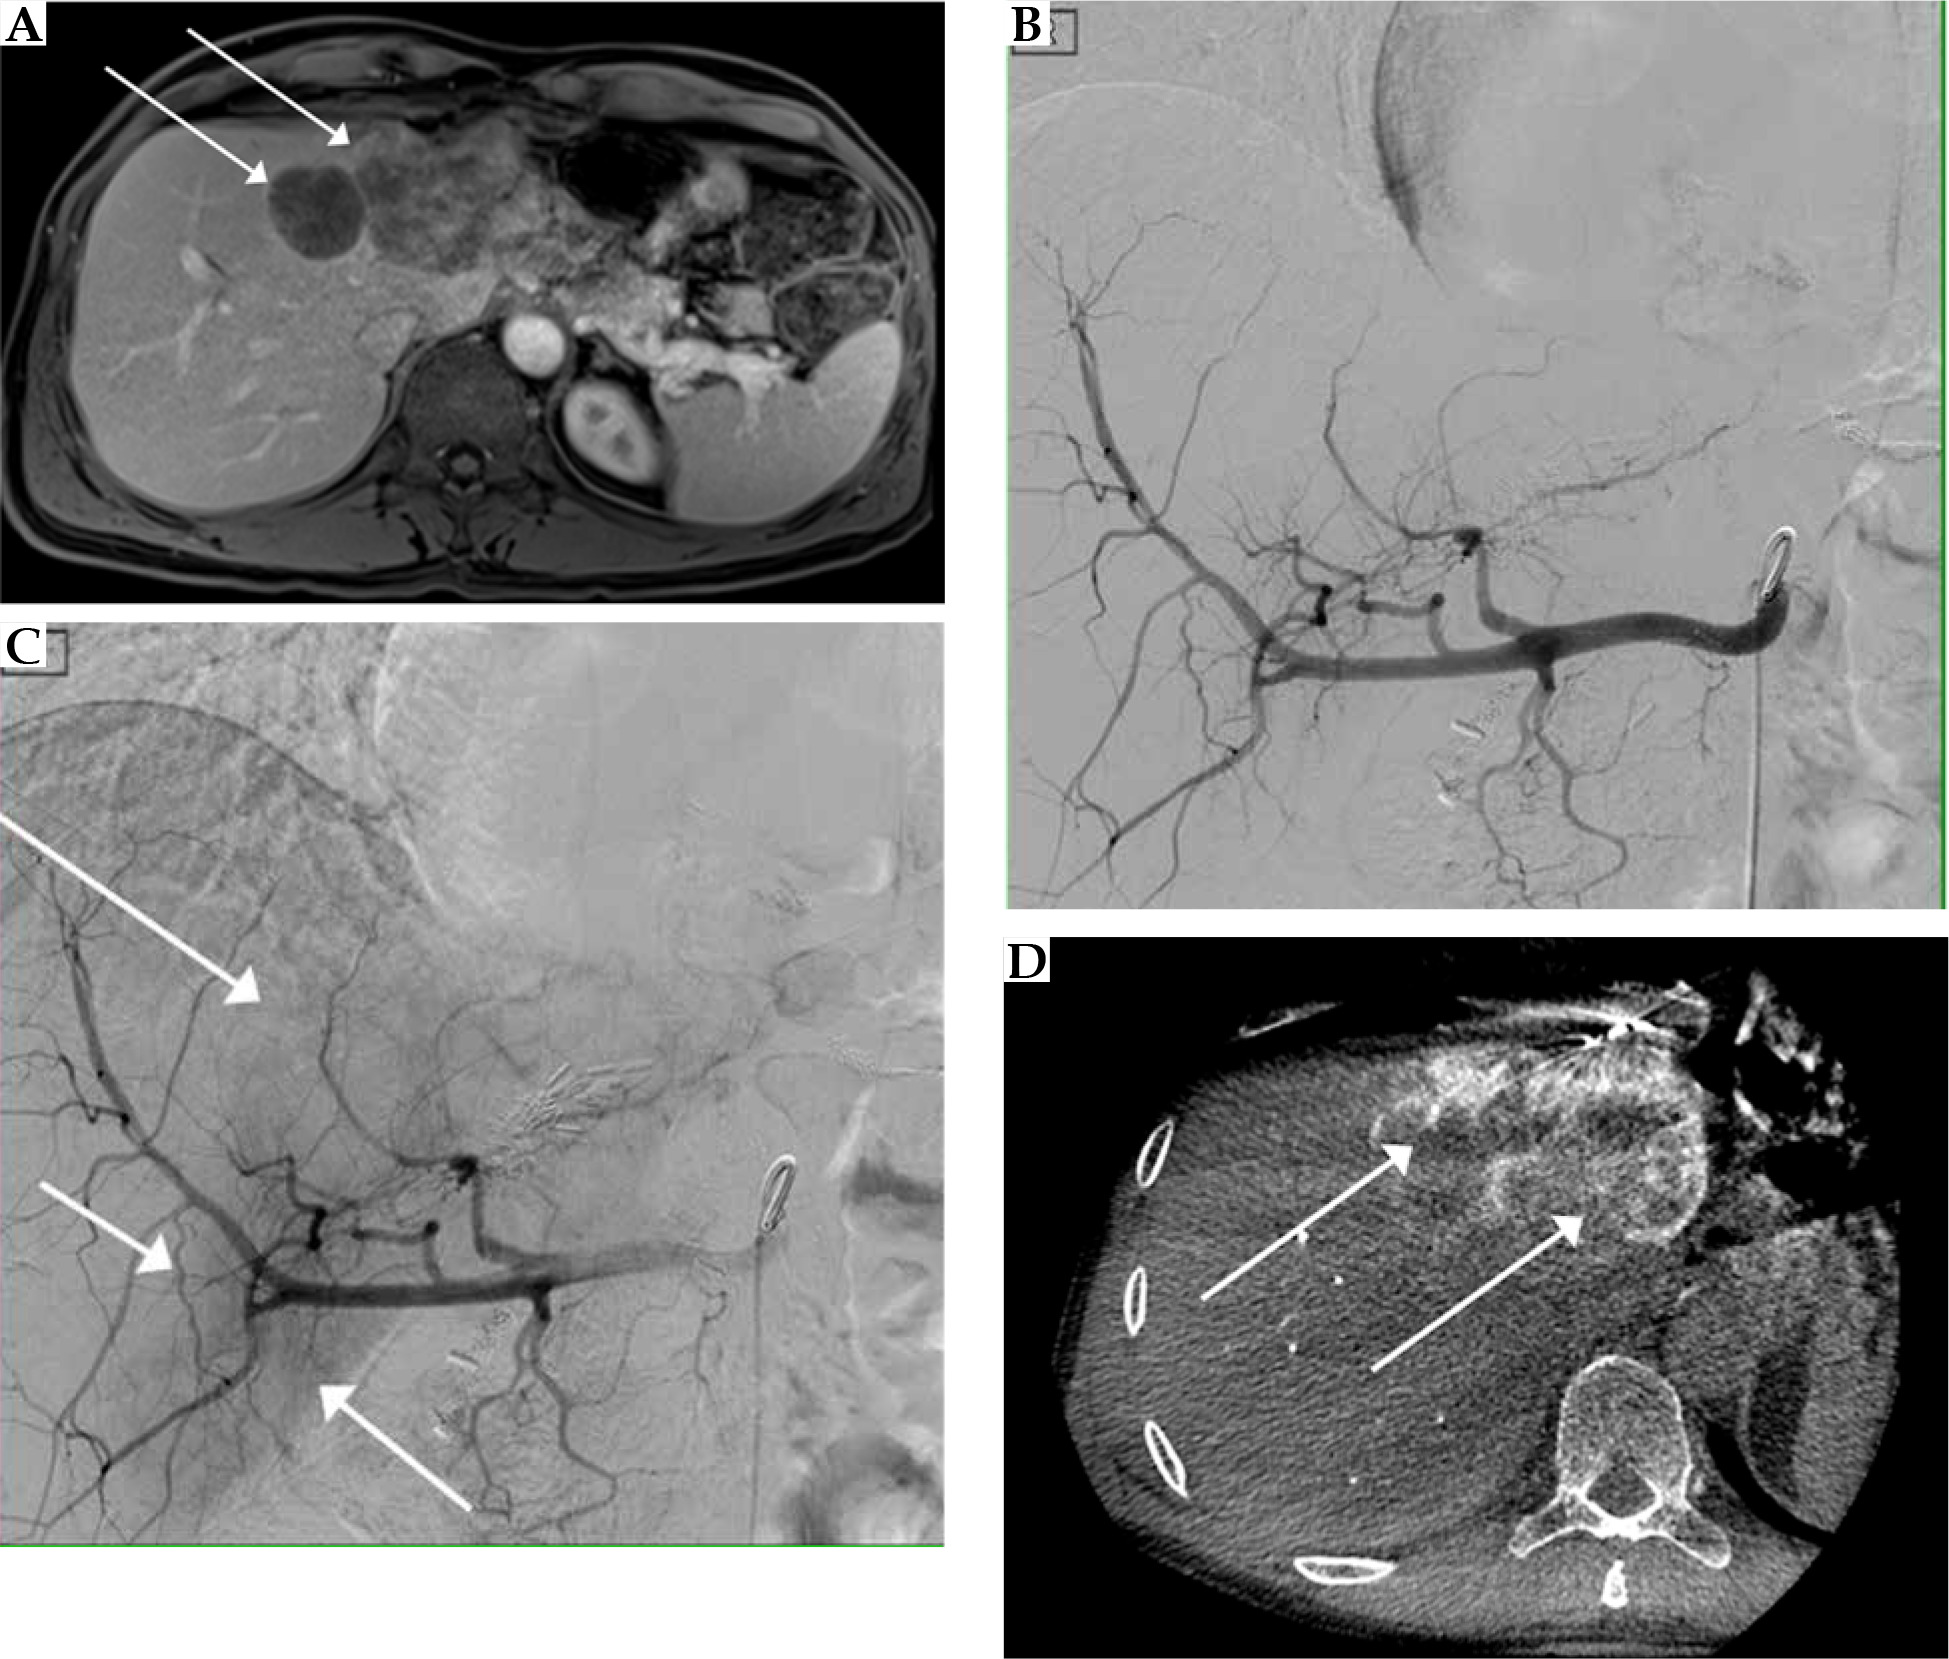

Initial imaging was performed with a 1.5 Tesla contrast-enhanced MRI of the liver with Gd-EOB-DTPA (e.g., Primovist®, Bayer Vital, Leverkusen, Germany; Figure 1) and a CT of the thorax to control for new extrahepatic metastases or consolidations. Laboratory workups were performed on the day before and after each intervention to assess blood count toxicity. Immediate follow-up examinations occurred the day after each intervention, including sonography of the liver or the punctured femoral artery. Post-interventional control imaging was scheduled in 3-month intervals using contrast-enhanced CT or MRI of the abdomen.

Fig. 1

Pre- (A, B) and 60-days post-interventional MRI (C) in a patient with colorectal liver metastases in the left liver lobe after treatment with irinotecan transarterial chemoembolization and CT-guided high-dose-rate brachytherapy. A) Fat-saturated T1 transverse sequence after Gd-EOB-DTPA-injection in the portal venous phase with an inhomogeneous enhancement of the liver metastases in liver segments II and IVa (arrows); B) Fat-saturated T1 transverse sequence with missing Gd-EOB-DTPA-retention in the liver metastases (dashed arrows); C) Fat-saturated T1 transverse sequence with missing Gd-EOB-DTPA-retention in the liver metastases as well as perifocally corresponding to irradiation volume (dotted arrows)